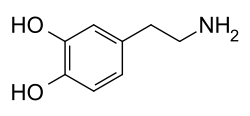

Psychoactive drugs are divided into different groups according to their pharmacological effects. Commonly used psychoactive drugs and groups are listed below:

- Stimulants (colloquially referred to as "uppers"). This category comprises substances that increase wakefulness and productivity, stimulate the nervous system, and may cause euphoria, but are not known to typically cause hallucinatory effects. Some stimulants are used medicinally to treat individuals with ADHD and Narcolepsy.

- Examples: amphetamines, caffeine, cocaine, nicotine

Psychoactive drugs operate by temporarily affecting a person's neurochemistry, which in turn causes changes in a person's mood, cognition, perception and behavior. There are many ways in which psychoactive drugs can affect the brain. Each drug has a specific action on one or more neurotransmitter or neuroreceptor in the brain.

Drugs that increase activity in particular neurotransmitter systems are called agonists. They act by increasing the synthesis of one or more neurotransmitters, by reducing its reuptake from the synapses, or by mimicking the action by binding directly to the postsynaptic receptor. Drugs that reduce neurotransmitter activity are called antagonists, and operate by interfering with synthesis or blocking postsynaptic receptors so that neurotransmitters cannot bind to them.[51]